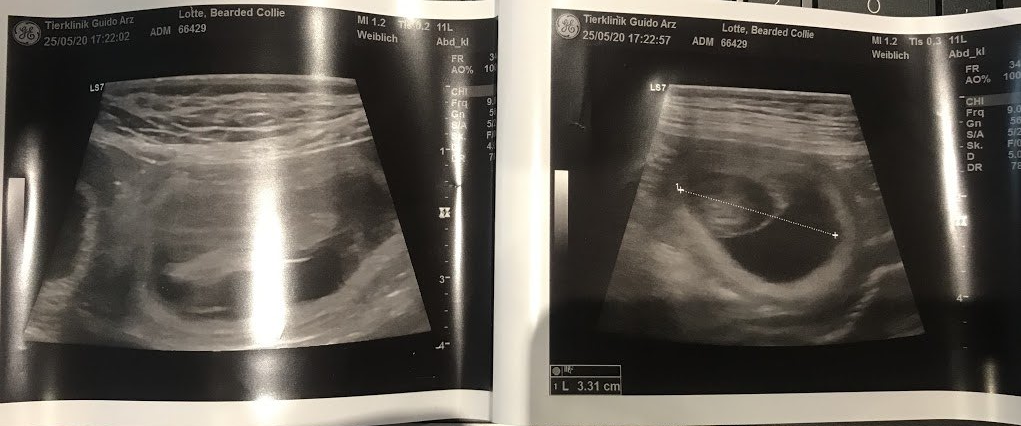

小家伙们已经在轻轻敲门了……乐天放松的时候,你不仅可以看到它,还可以感觉到它。这是一个不可思议的奇迹,让我充满了幸福。她的腰围增加了很多,她的动作更加缓慢和从容。其实,乐天很灵活,可以像椒盐卷饼一样弯曲😂但是现在她的肚子挡住了,当它挠耳朵的时候,她想挠它……然后她不得不窒息一下。

我们非常期待它......不会太久,紧张局势正在上升......鹳已经在房子周围飞来飞去。